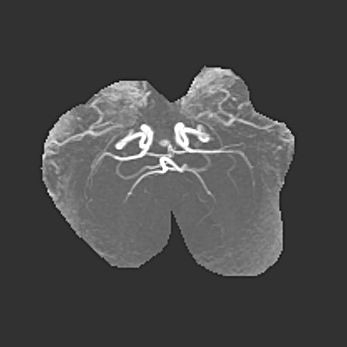

Подострая гематома правой гемисферы мозжечка.

Наружная гидроцефалия.

Возраст: 15 дней

Вес: 3100 г

Пол: женский

Окружность головы: 37 см

Срок гестации: 35-36 недель

При открытой наружной форме гидроцефалии у новорожденных расширяются и переполняются субарахноидные пространства.

Кровоизлияния в мозжечок имеют две клинико-анатомические формы: полушарные гематомы и кровоизлияния в червь.

К появлению этой патологии может привести: повреждения головного мозга, возникающие в результате асфиксии и гипоксии плода при беременности, или травмы во время родов. Редко гематома мозжечка может быть результатом первичной коагулопатии и сосудистой мальформации, диссеминированном внутрисосудистом свертывании, изоиммунной тромбоцитопении.